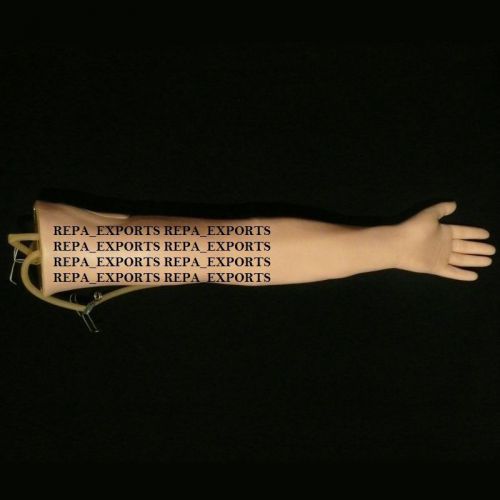

Injection-Training-Arm-Human-Anatomical-Model